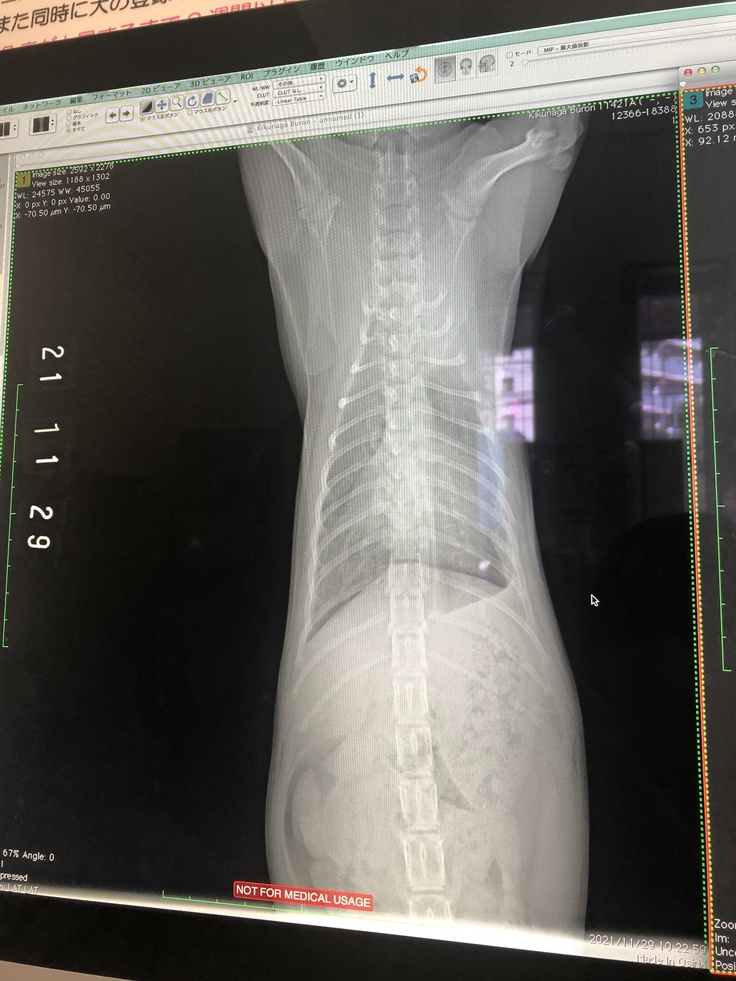

11月29日 治療43日目 7週目通院

血液検査 赤血球容積比 ↑、白血球数 ↓、血小板 ↑、A/G比 0.77 ↑

A/G比が目標値0.7を超えました。

レントゲン検査

左肺の胸水も減ってきて、黒い部分がかなり広がってきました。

抗体価検査の結果は後日となります。